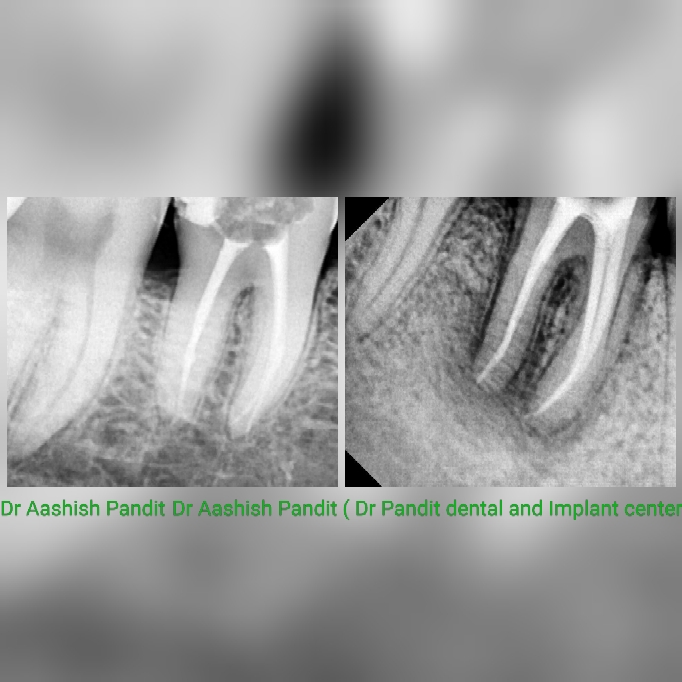

Root canal is a treatment to repair and save a badly damaged or infected tooth instead of removing it. The procedure involves removing the damaged area of the tooth (the pulp) and cleaning and disinfecting it, then filling and sealing it Established in 2013 Dr Pandit's dental clinic provides quality dental treatment ! Single visit root canal treatment, dental implants, gums treatment, dentures, braces, bleaching, cosmetic dentistry etc . Dentist in janakpuri, sagarpur , vashist park, Delhi, best dental clinic, Dr Aashish Pandit , Dr Preeti kaushik.